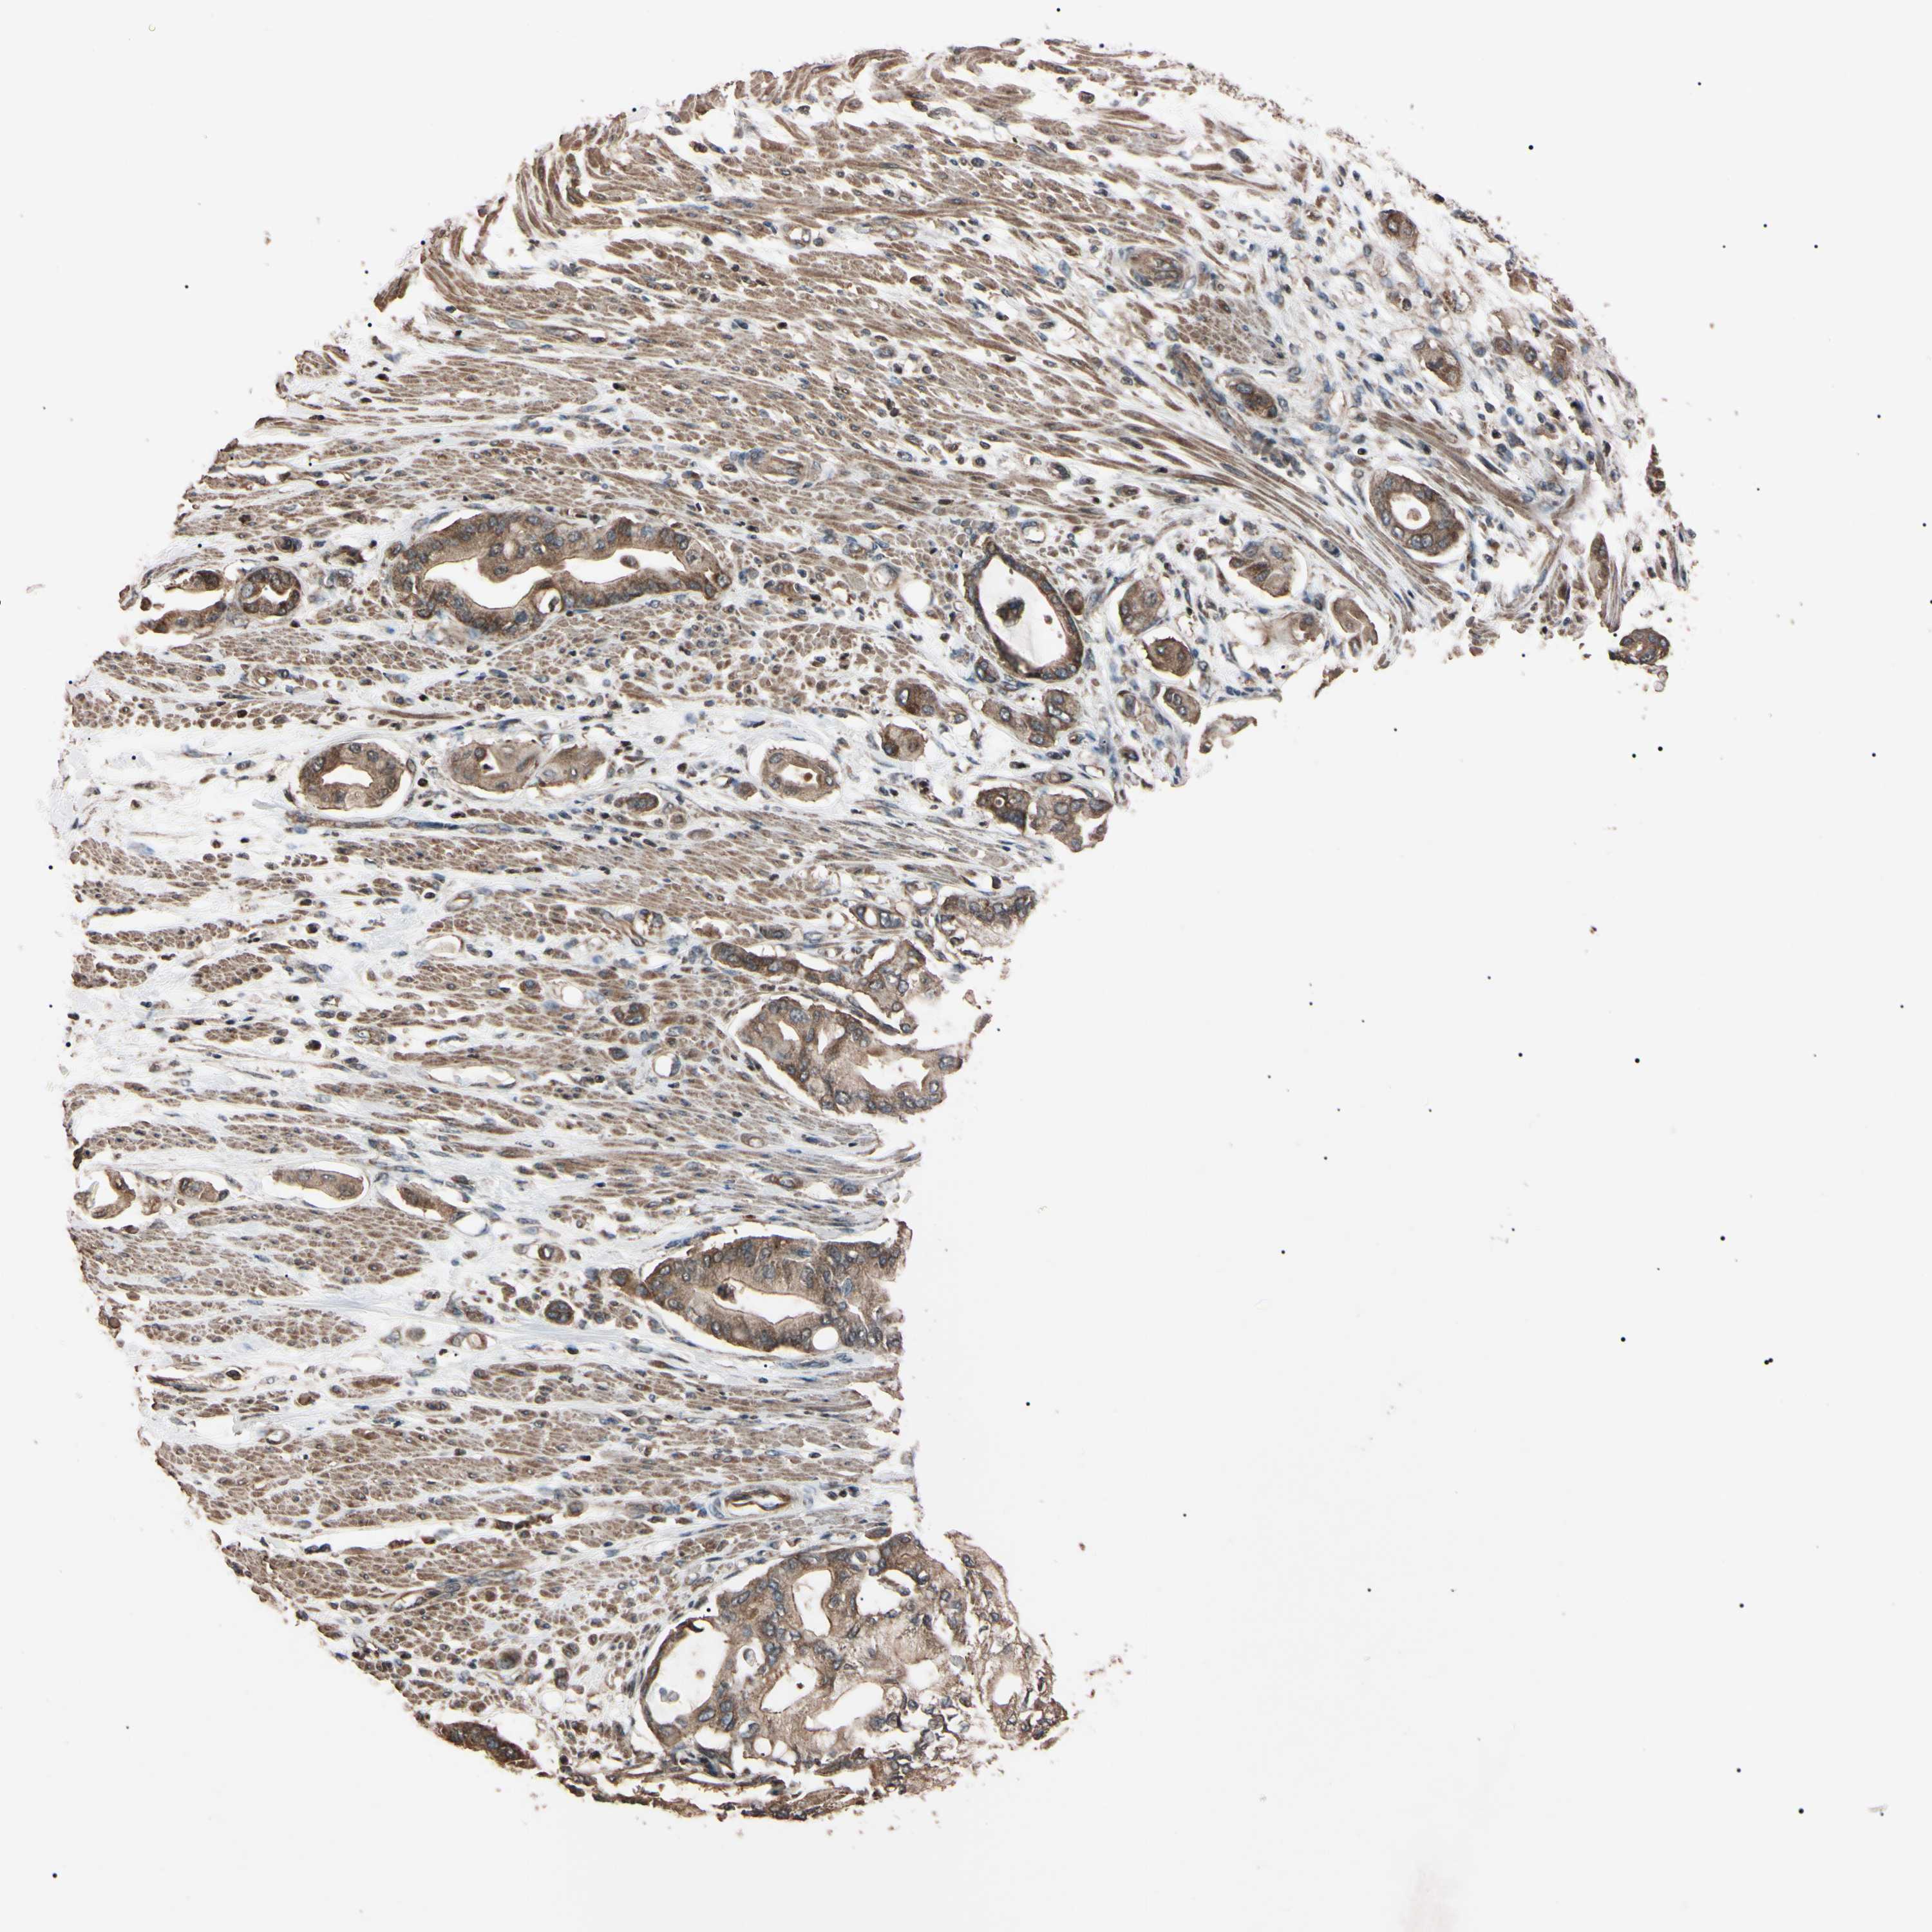

PANCREATIC CANCER - Protein expressioni

A mouse-over function shows sample information and annotation data. Click on an image to view it in a full screen mode. Samples can be filtered based on level of antibody staining by selecting one or several of the following categories: high, medium, low and not detected. The assay and annotation is described here.

Note that samples used for immunohistochemistry by the Human Protein Atlas do not correspond to samples in the TCGA dataset.

Antibody stainingi

Antibody staining in the annotated cell types in the current human tissue is reported as not detected, low, medium, or high, based on conventional immunohistochemistry profiling in selected tissues. This score is based on the combination of the staining intensity and fraction of stained cells.

Each image is clickable and will lead to virtual microscopy that enables deeper exploration of all samples and also displays staining intensity scores, fraction scores and subcellular localization as well as patient and tissue information for each sample.

Antibody HPA004102

Antibody CAB010309

Staining

High

Medium

Low

Not detected

Intensity

Strong

Moderate

Weak

Negative

Quantity

>75%

75%-25%

<25%

None

Location

Nuclear

Cytoplasmic/membranous

Cytoplasmic/membranous,nuclear

Adenocarcinoma, NOS

Adenocarcinoma, metastatic, NOS